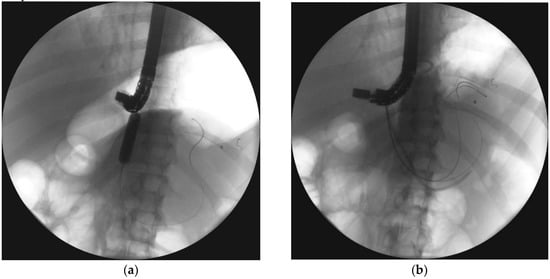

Figure 8.

ERP during endoscopic treatment of pancreatic necrosis. (a) Complete disruption of the pancreatic duct can be seen within the tail at the level of transmural stent. (b) The stent bridging the pancreatic duct disruption. ERP, endoscopic retrograde pancreatography.

Partial disruption of the pancreatic duct (Figure 8a,b) is diagnosed when the pancreatic duct fills with contrast distal to the disruption site [55]. Complete disruption (Figure 9a) describes contrast extravasation outside the duct without contrast filling the distal part of the main pancreatic duct [69]. In the course of ANP, partial disruption of the pancreatic duct is more common than complete disruption [25]. Additionally, it is possible to observe no contrast spilling out of the duct (no visible disruption of the pancreatic duct) on ERP in some patients following ANP [25].